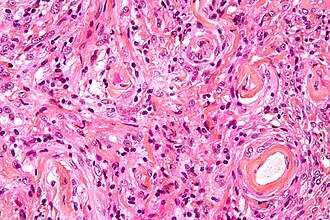

Angiomatous meningioma

- AKA vascular.

- May bleed like stink.

- May show extensive edema.

- Hyalinized vessels dominate over tumor cells.

- Degenerative nuclear atypia.

DDx:

- Vascular malformatons

- Hemangioblastoma

- Angiomatous meningioma HE x100.jpg

Angiomatous meningioma (WC/jensflorian)